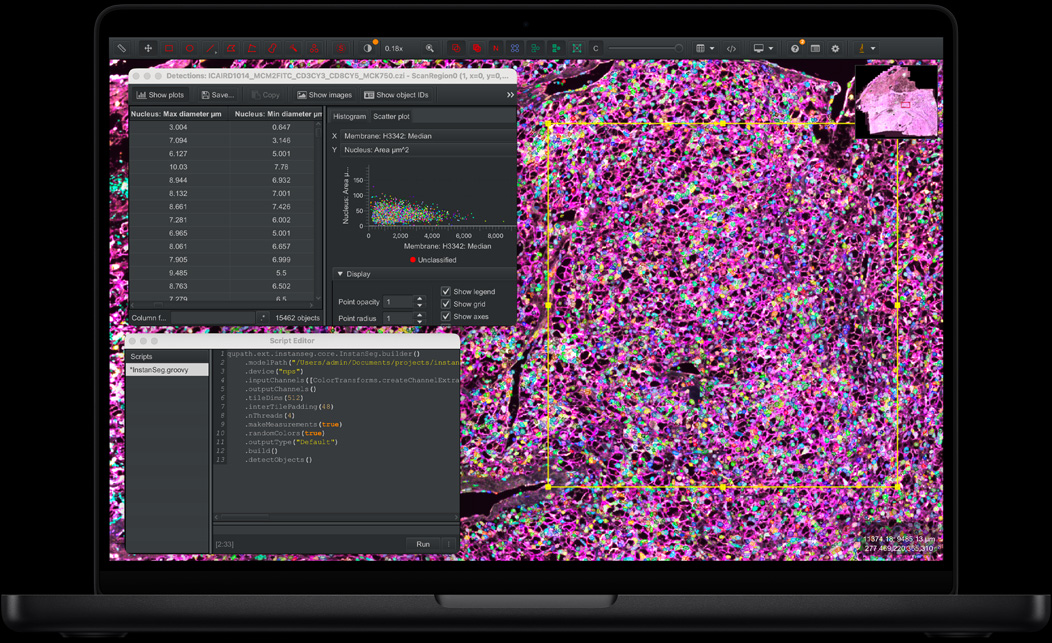

QuPath、Instanseg

M5 Pro 將一切加速,由編譯程式碼、DNA 測序,以至剪輯多個 8K ProRes 影片串流,可滿足一眾追求極致的用家。無論你選擇 14 吋或 16 吋型號,配備 M5 Pro 的 MacBook Pro 都能讓你輕鬆應付高要求的工作流程,以及 AI 為本的各項任務。它有多達 20 核心 GPU,帶來矚目的圖像處理效能,大大提升 3D 算圖及動畫製作速度。起始儲存空間現在有 1TB 或 2TB,為你提供更大發揮空間,成就種種精彩。